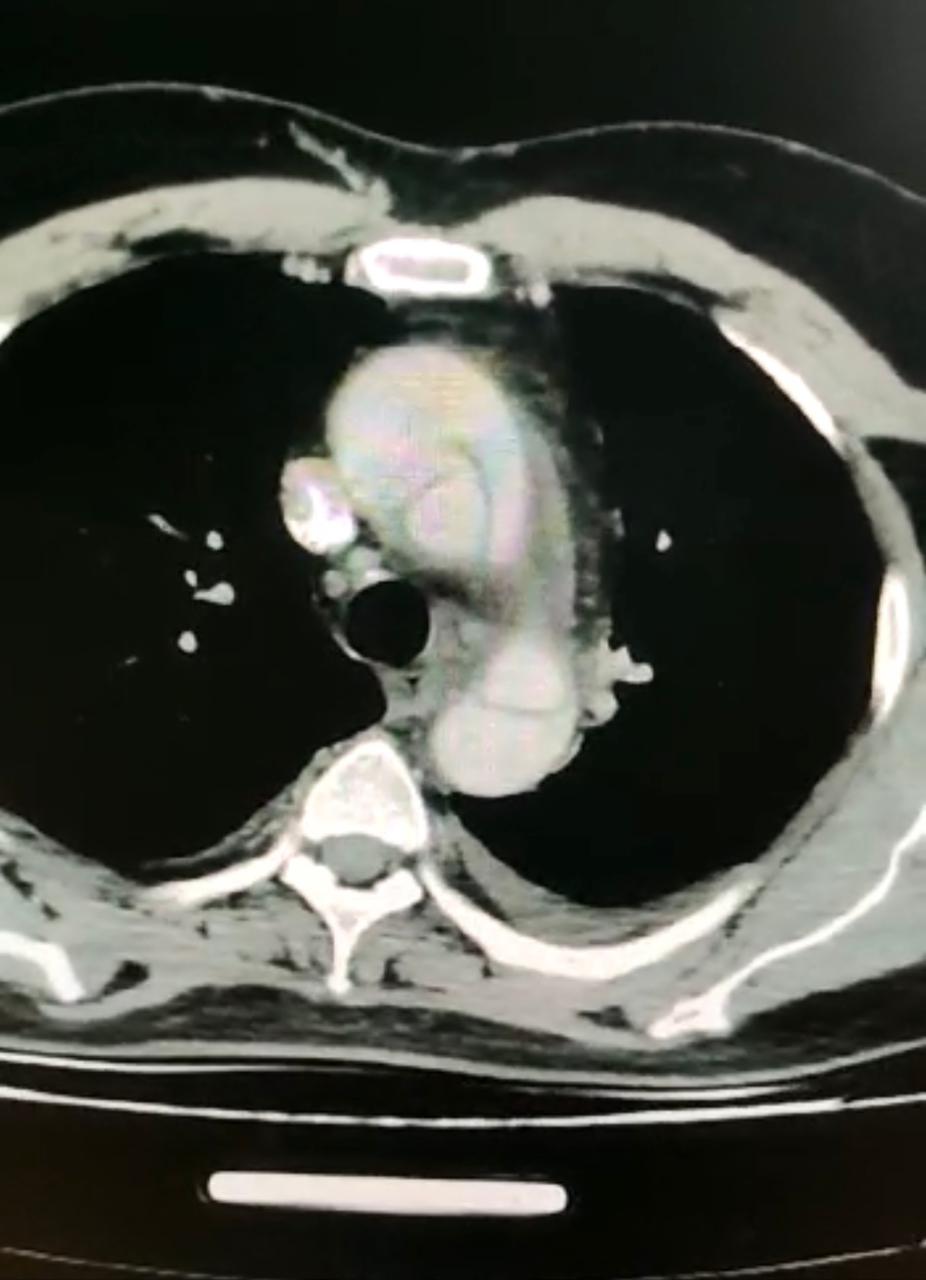

و حول تفاصيل الحالة كشف الدكتور حسام العربي مدير مستشفى القلب الجامعى أن الحالة كانت تعانى من الآلم شديدة بمنطقة الصدر وأعلى الظهر و بعد  إجراء الفحوصات تحت إشراف  الأطباء بقسم أمراض القلب تبين أن المريض  يعانى من انشطار بالشريان الأورطى مع عدم استقرار الحالة الصحية وعلى الفور تم تجهيز المريض للدخول إلى عمليات بشكل عاجل و طارئ واستغرقت العملية 6 ساعات .